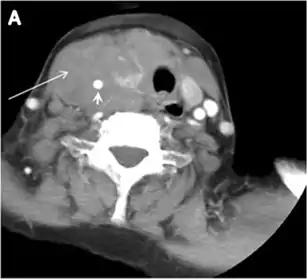

Parathyroid adenoma (PA) is the most common cause of primary hyperparathyroidism. Ectopic parathyroid adenoma is rare. The third and fourth pharyngeal pouches represent the embryological origin of the parathyroid tissues, and ectopic parathyroid adenoma can ultimately develop anywhere along their migration course. In a large retrospective study of patients with primary hyperparathyroidism, PA was detected in the intra-thyroid location in 0.7% of cases. In another retrospective analysis of 202 patients with ectopic PA, intra-thyroidal location was found in 18% of the cases. Intra-thyroid parathyroid adenomas mimic thyroid nodules in CT scans and may even show uptake on a thyroid iodine scan. Correlation with laboratory workup, including measurement of serum parathyroid hormone and calcium level, is required. In addition, the evaluating radiologist should search for radiological manifestations of hyperparathyroidism, such as osteopenia, bone resorption, and brown tumours (Fig. 22).[1]